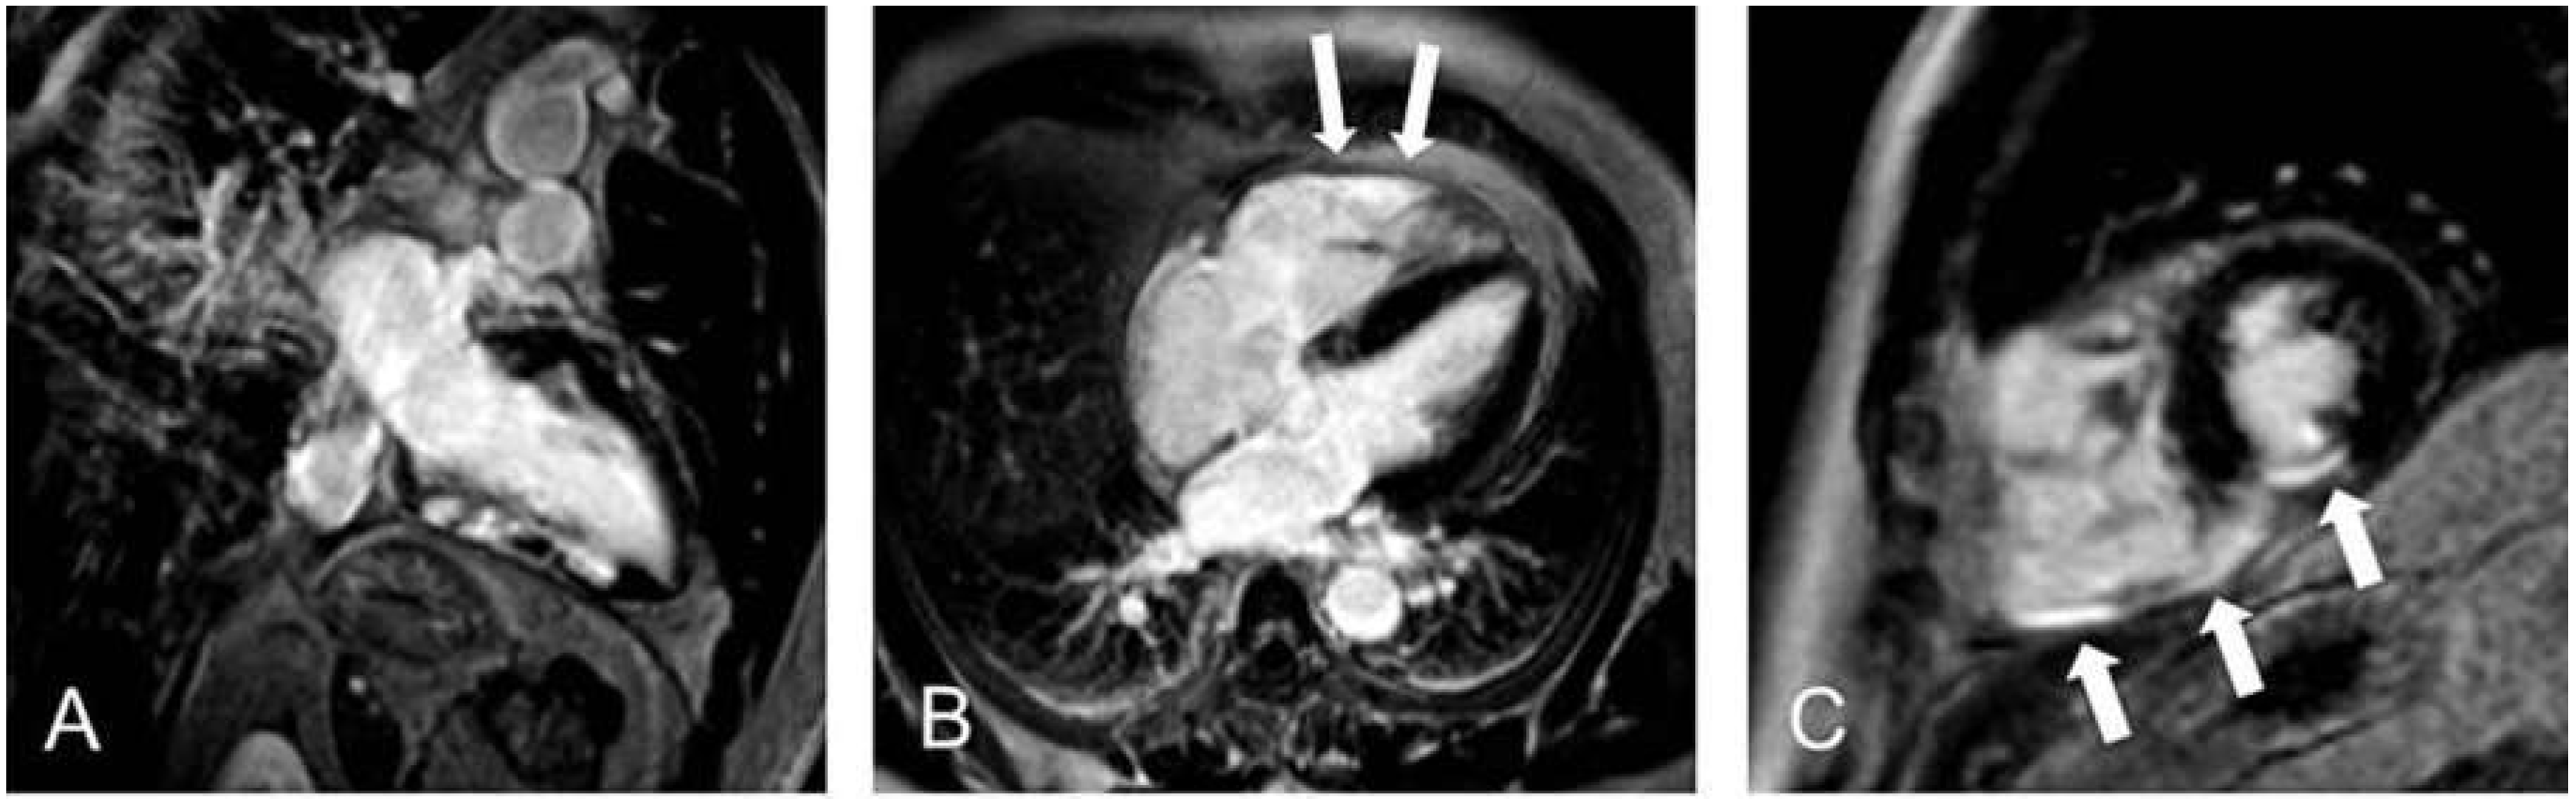

Viables Myokard und Narbengewebe

Figure 3. Late-gadolinium-enhancement-Aufnahmen eines Patienten nach Hinterwandinfarkt. (A) 2-Kammer-Blick (B) 4-Kammer-Blick (C) Kurzachsenorientierung LV/RV. Deutlich zu sehen ist die Beteiligung des rechtsventrikulären Myokards (B,C).